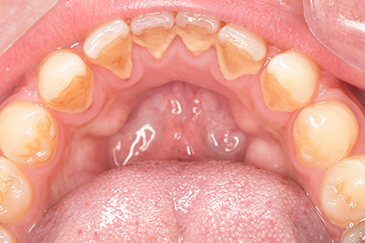

CASE 4

Before

After

基本情報

| 年齢・性別 | 52歳・女性 |

| 主訴 | クリーニングしたい |

| 治療内容 | スケーリング・PMTC |

| 治療期間 | 60分 |

| 治療費 | 約7,000円 |

| リスク・副作用 | 知覚過敏、歯肉退縮 |

| 治療方針 | 歯石とステインを除去して、今後は定期検診でのクリーニングと併せてガムピーリングやホワイトニングを行います。 |

| 担当者所見 | 歯肉の色素沈着が目立つため、ガムピーリングを行いながらホワイトニングを行うことをおすすめします。 |